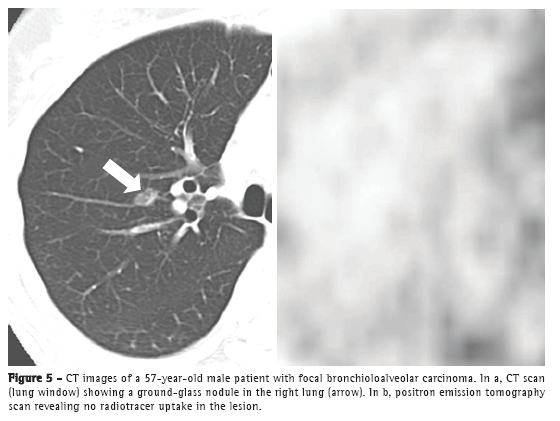

However, it is of note that pure BAC might not show increased 18F-fluorodeoxyglucose (FDG) uptake,(6) given that these tumors are usually indolent, slow growing, and well differentiated. Therefore, the lack of FDG uptake does not exclude the possibility of neoplasms, such as BAC, small lesions, and indolent cancers. Martins et al.(17) studied the diagnostic accuracy of PET in the assessment of solitary pulmonary nodules and obtained, among the 32 patients studied, only one false-negative result, a case in which the final diagnosis was BAC. Therefore, CT analysis is mandatory for the diagnosis (Figure 5).